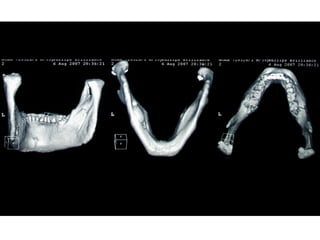

Eliminación de focos sépticos en bloque en paciente con osteitis

mandibular crónica

Osteomielitis

La osteomielitis es una infección súbita o de larga data del hueso o médula

ósea, normalmente causada por una bacteria piógena o micobacteria y

hongos. Los factores de riesgo son trauma reciente, diabetes, hemodiálisis y

drogadicción intravenosa.

La Osteomielitis se define como una inflamación extensa del hueso,

implicando a toda porción esponjosa, medular, cortical, periostio, vasos

sanguíneos, nervios y epífisis. La inflamación puede ser aguda, subaguda o

crónica y presenta un desarrollo clínico diferente según su naturaleza (1-5).

En el caso de los maxilares se considera la infección odontógena como la

causa más frecuente de osteomielitis. Se puede presentar a cualquier edad

con un predominio entre los hombres. Afecta principalmente al maxilar

inferior. En el maxilar superior es más raro, debido a una mayor

vascularización .